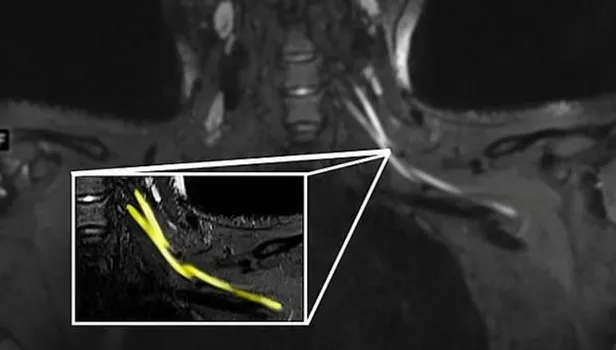

Son dakika haberi! Bilim insanları uzun süreli yeni tip koronavirüs (Kovid-19) hastalarında görülen yorgunluk ve ağrının sebebini ilk kez ortaya koydu. ABD’de yer alan Northwestern Üniversitesi’nden araştırmacılar MRI ve ultrason tekniklerini birleştirerek, geleneksel yöntemlerle tespit edilemeyen Covid-19'un sinir sisteminde yarattığı hasarı kanıtladı. Geliştirilen yeni teknolojinin doktorlara, hastaları için uygun tedavi yöntemini belirlemesini sağlayarak hayat kurtarabileceği belirtildi.

NTV'nin haberine göre, Radiology dergisinde yayımlanan çalışmanın başyazarı Doktor Swati Deshmukh, konuya ilişkin yaptığı açıklamada, "Ağrı boynunuzdaki, dirseğinizdeki veya bileğinizdeki sorunlardan kaynaklanıyor olabilir ve bunu anlamanın en iyi yolu MRI veya ultrasondur.

Yaptığımız çalışmayla çok küçük sinirleri bile gösteren gelişmiş görüntüleme sunuyoruz. Bu da sorunun nerede olduğunu tespit etmemize, ciddiyetini değerlendirmemize ve buna neyin neden olabileceğini önermemize yardımcı oluyor" ifadelerini kullandı.

Öte yandan, çalışmanın yazarları gelişmiş ultrason teknolojisinin kolay taşınabilir ve ucuz olduğunu, ayrıca sinir hasarını tespit etmede tomografiden daha iyi olduğunu ifade etti.

Araştırmacılar, taramaların doktorların hastaları bir rehabilitasyon uzmanına mı yoksa daha ciddi durumlarda bir cerraha mı sevk edeceklerine dair karar vermelerine yardımcı olacağını aktararak, "Eğer görüntüleme enflamatuar bir tepkiye bağlı sinir hasarı bulursa, hastaya bir nöroloğa görünerek daha iyi hizmet edilebilir.

Görüntüleme, hematomdan kaynaklanan sinir hasarını ortaya çıkarırsa, kan sulandırıcı ilaçların derhal ayarlanması gerekir ve hatta hastanın bir cerrahı görmesi gerekebilir" açıklamasını yaptı.